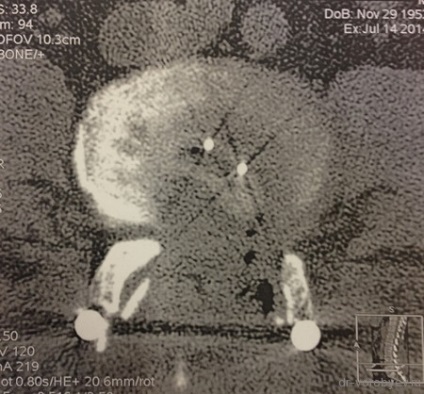

CT-vizsgálat - axiális vetületben. Lásd a körvonalak Cage kimetszett facet sustatv.